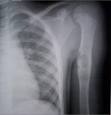

Las radiografías simples son suficientes para diagnosticar el QOU una vez que el observador está familiarizado con la apariencia de la lesión. La lesión aparece como una zona osteolítica bien definida por un margen esclerótico. La lesión rellena y en ocasiones expande la metafísis juxta-epifisial del hueso.

La lesión es relativamente simétrica con respecto al eje medio del hueso, no atraviesa la corteza ni forma masas extraóseas. No hay reacción periosteal visible a menos que haya historial de fractura previa. Fragmentos de corteza que se encuentren en posiciones dependientes dentro del quiste, son conocidos como el signo de “hojas caída” o “fragmento caído”. Estudios de tomografía axial computadorizada (TAC) son útiles solo cuando la lesión esté localizada en la pelvis.